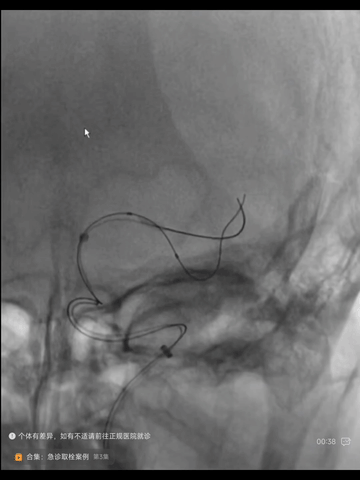

撤出synchro导丝,经Transend导丝送入微导管到M2,经微导管于左MCA主干植入一枚颅内自膨式支架(EP2 4*23mm),后造影示:支架位置佳,展开贴壁良好,主干狭窄解除,下干起始部未见明显狭窄。